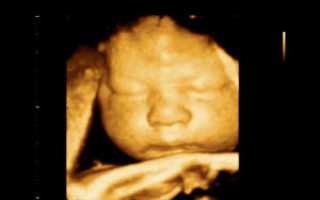

При классическом виде УЗИ на монитор выводится плоская картинка — проекция внутренних органов на плоскость. 3Д УЗИ даёт объёмное изображение, а 4Д УЗИ позволяет продемонстрировать видео — в реальном времени можно увидеть все движения ребёнка, рассмотреть его черты лица, оценить его состояние.

4Д УЗИ позволяет увидеть не плоское изображение малыша, а объёмное видео

Трехмерное изображение представляется в 3 измерениях — глубине, высоте и ширине. Беременная может увидеть ребенка на экране УЗИ-аппарата в цвете. При этом детально просматривается каждая часть лица и тела, мимика плода.